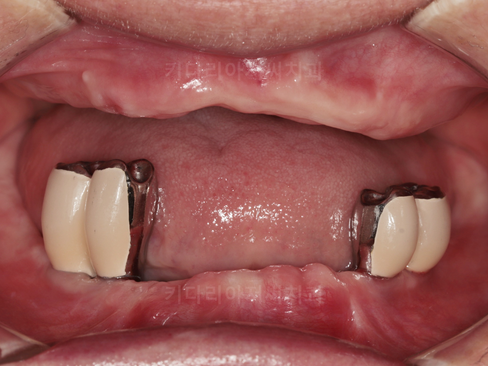

부산보험임플란트 키다리아저씨치과에 처음 오셨을 때의 입안 사진입니다.

전체적으로 치석이 많이 침착되어 있으며 잇몸이 부어있고, 어금니 결손으로 씹는 기능이 안되다 보니 전체적으로 치아들이 많이 정출되어 있습니다.

또한 앞니 보철과 치아 뿌리가 분리되어 보철이 흔들리는 상태였습니다.